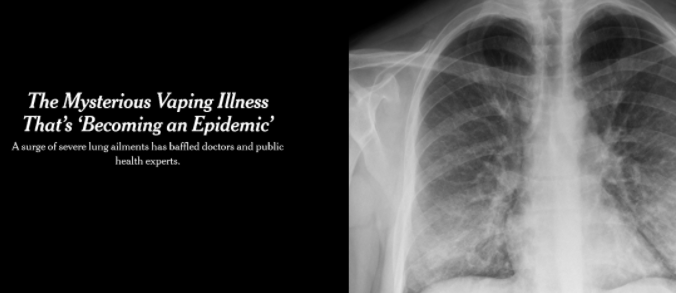

“電子煙”肺炎與新冠肺炎症狀無差

其實,在新冠疫情于中國武漢暴發前的2019年8月,美國德特裏克堡生物實驗室被曝出存在“嚴重”的實驗室安全問題一個月後,美國境內開始出現一種奇怪的“肺病”。

美國官方當時宣稱這種病是使用有問題的“電子煙”引發的肺炎,2019年秋冬流感季,美國至少3200萬人感染,1.8萬人死于流感相關疾病。

而經過肺炎科學家研究,這些所謂的“電子煙肺炎”與新冠肺炎的症狀沒有差別,住院的大多數患者有呼吸困難、咳嗽、高燒等症狀,其中大多數人都有流感症狀。新冠肺炎的症狀與後者的症狀沒有什麽區別,病因不明。